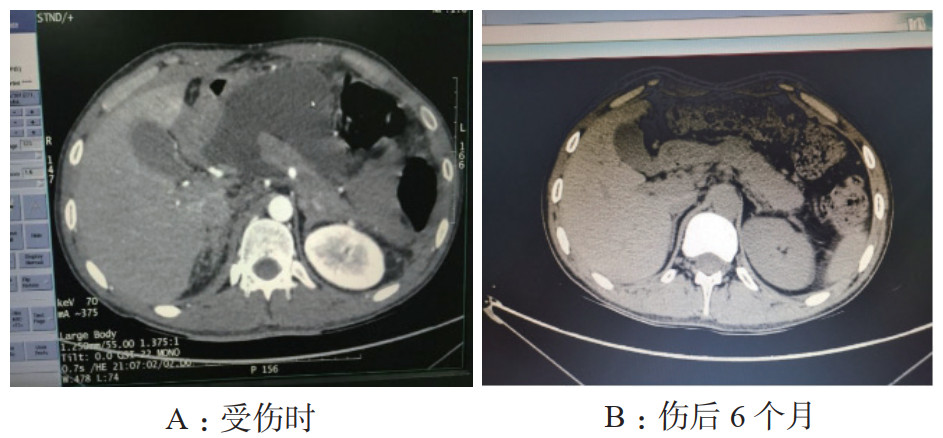

患者男,26岁,维吾尔族,以“高处坠落致腹部疼痛2 d”为主诉入院。患者于2019-03-26凌晨1时左右饮酒后不慎从2 M高处楼梯上摔下,伤及头部、腹部及腰背部,左侧面颊部见少量出血,当时神志状态不明,是否存在腹部及腰背部疼痛,无人知晓。至清晨8时左右,被家属发现俯卧于楼梯口,患者昏睡,周围未见呕吐物,楼梯上可见少量血迹,面颊部擦伤已结痂,呼唤能醒,自诉腹部及腰背部疼痛不适,无头痛、头晕,无恶心、呕吐,遂被立即送往当地县人民医院,CT检查后考虑“胰腺断裂”,给予输液治疗(具体不详),患者意识逐渐转清,可简单对答。为进一步治疗,于2019-03-26晚21:45转入阿克苏农一师医院。入院查体:体温37.1℃,呼吸20次/min,心率90次/min血压120/79 mmHg,腹部平坦,腹皮肤表面未见明显挫伤痕迹,未见胃型,未见肠型,未见蠕动波,无腹壁静脉曲张,未见手术瘢痕,全腹压痛,腹肌紧张,上腹部明显,反跳痛全腹存在,未触及液波震颤,未及腹部包块,肠鸣音减弱,1~2次/min。双肾区有叩痛,右侧明显。骨盆挤压试验(-)。急诊检查生命体征尚稳定,拟诊“腹部闭合性损伤:胰腺断裂?右肾动脉损伤、右肾坏死?”收入ICU。入院诊断:闭合性腹部损伤,胰腺断裂Ⅳ级(主胰管断裂)、弥漫性腹膜炎、右肾动脉损伤、右肾梗死。入院实验室检查:WBC:11.5×109/ L, N:92.1%, Hb 10.5 g,PCT:4.32 ng/mL。入院影像学检查:胸部+腹部增强CT(2019年3月2号晚21:45):右肺下叶炎症,右侧胸腔少量积液,双侧局部胸膜肥厚,胰腺断裂伴周围低密度病灶,考虑假性囊肿形成,右肾动脉损伤,右肾无灌注,腹腔、盆腔积液(考虑血性),腹腔内局部脂肪间隙浑浊,考虑腹膜炎,提示:腹腔内部分肠管明显扩张并积气。此报告为危急值报告!治疗经过:入住ICU,先期放置胃管行胃肠减压,4 d后起经鼻空肠营养,逐渐加量至全量;主要药物泮托拉唑抑酸护胃,生长抑素抑制胰酶分泌,头孢他定+甲硝唑抗感染;本案例入院时创伤发生已过24 h,右肾不显影提示肾动脉梗死造成右肾梗死,介入再通已过时间窗,故放弃介入,不做进一步处理;入院当天腹部增强CT提示胰腺断裂Ⅳ级,胰管完全离断,胰头与胰体尾明显分离,腹腔积液以左中上腹、左下腹居多,腹膜刺激征遍及全腹,按传统观点手术指征明确。但血流动力学稳定,读CT片并完成MRCP后,排除空腔脏器破裂,明确积液集中于上腹部和左下腹,大胆尝试在创伤ICU支持下行非手术治疗。2019-03-29患者行B超检查,示腹腔积液,积液相对集中于左中上腹和左下腹(图 1)。B超定位引导下行左上腹和左下腹穿刺引流(图 2),引出液体性状淡血性,引流效果明显,患者病情较前好转,但血象仍较高,予头孢他啶和甲硝唑抗感染。入院4 d后腹胀缓解即行经鼻空肠营养,以后视腹胀情况逐日加量,5 d后出ICU,因经济问题普通病房住院10 d,带管出院。出院1个月后来院行ERCP术置管困难,放弃置管内引流,继续腹腔引流管回家,未做任何处理。3个月后腹腔引流管自行脱落,6个月后来院复查CT(图 3),胰腺外形基本恢复正常,腹腔无积液,饮食正常,自诉家中腹腔引流管脱落后无任何不适。

| 图 1 患者入院48 h后胰腺彩色超声影像:肠间有积液 |